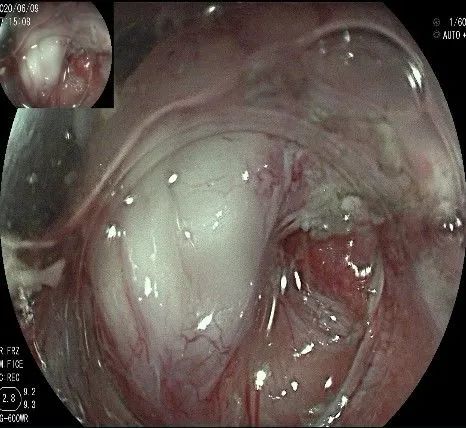

再次进镜观察,齿状线炎性息肉的地方,用圈套器圈套后通电切除。

瘤子切除后,在粘膜切开的地方,固有肌层的纵形肌处形成一个开口。

倒镜观察,隆起已经消失。

夹闭创面的时候做胃镜吸引,利于创面闭合。

创面夹闭完成,反复冲洗观察,无出血及穿孔。结束手术,等待病理结果。